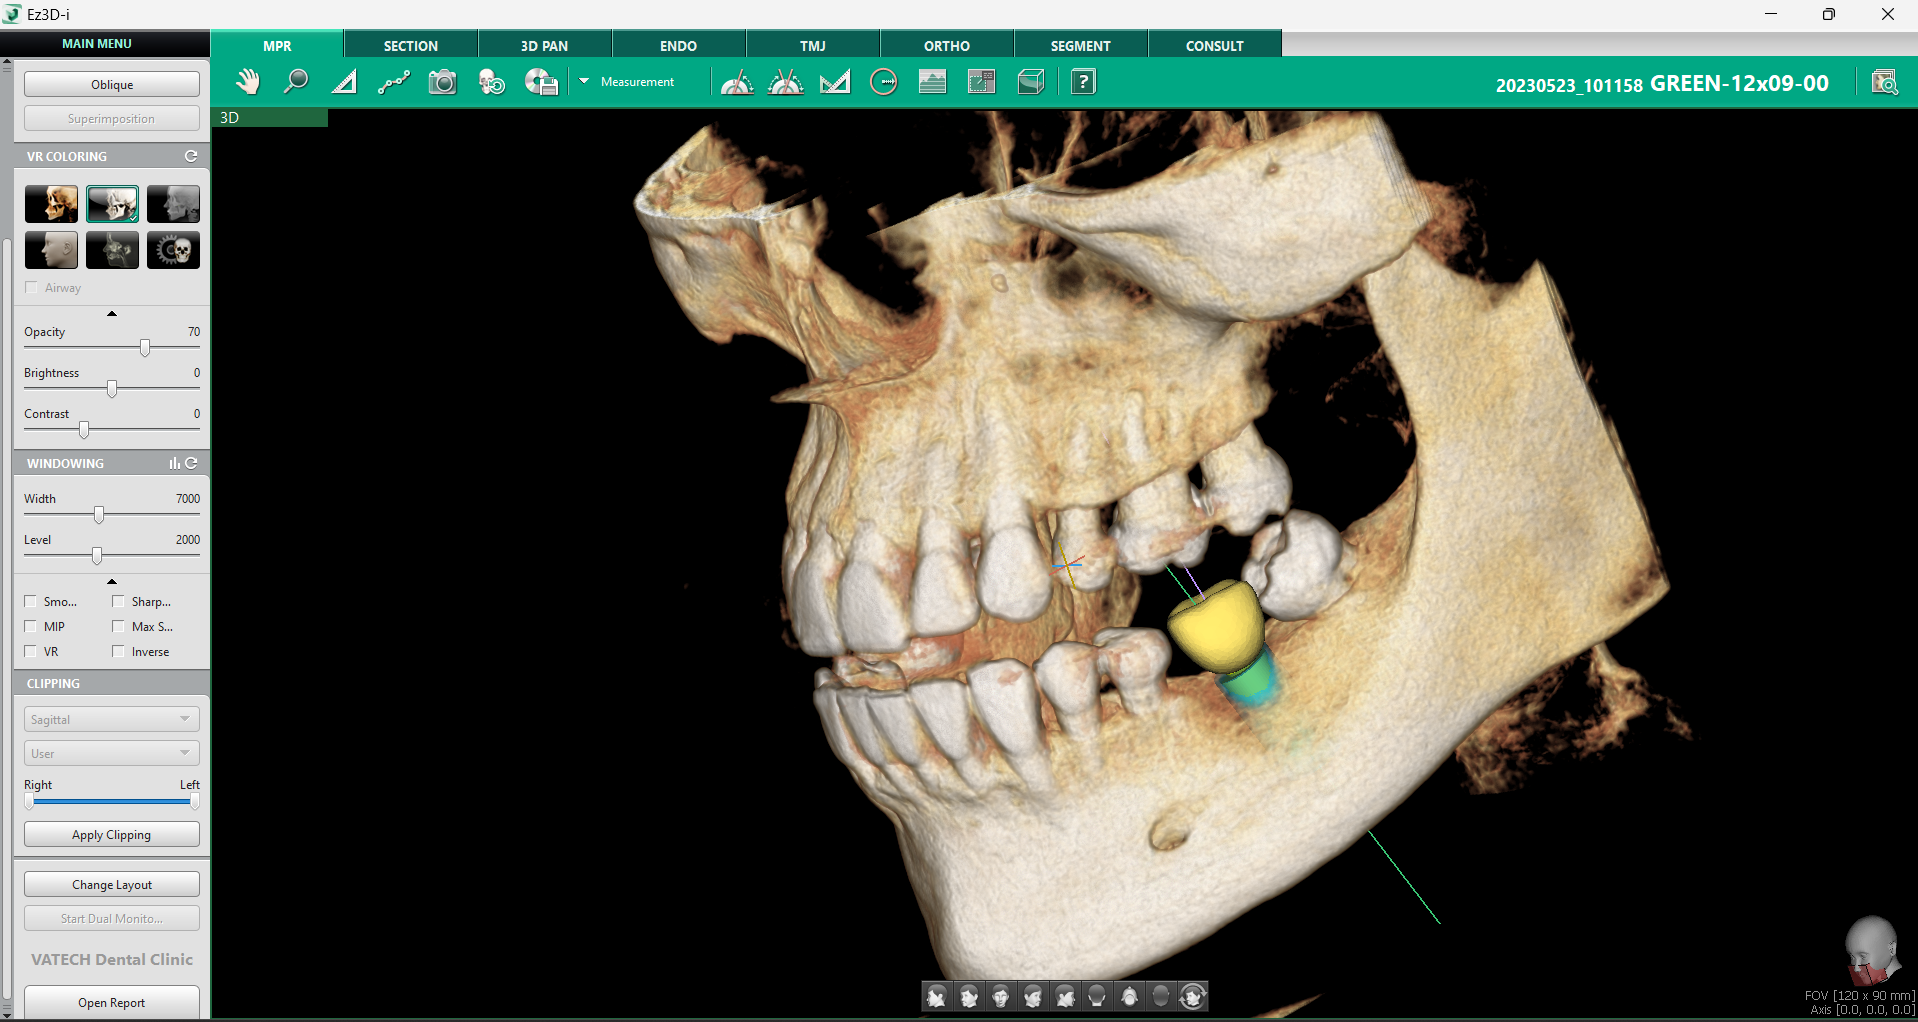

Odată selectată dimensiunea dorită printr-un click stânga, modelul implantului apare instantaneu în imaginea 3D, facilitând plasarea și verificarea sa în timp real.

2. Verificarea poziției implantului

În implantologie, verificarea poziției implantului este esențială pentru succesul procedurii și stabilitatea acestuia pe termen lung. Orice eroare de poziționare poate duce la complicații, de la integrarea deficitară a implantului în os, până la afectarea structurilor anatomice adiacente. Din acest motiv, Ez3D-i oferă o serie de instrumente avansate care permit verificarea multiplă a poziției în timpul plasării implantului, optimizând astfel fiecare etapă a procesului chirurgical.

Funcția Set MPR Axis este un instrument esențial pentru verificarea poziționării corecte a implantului, oferind o metodă rapidă și eficientă de analiză a sănătății osoase și a plasării implantului în raport cu structurile adiacente.

Printr-un simplu click dreapta pe implant și selectarea opțiunii „Set MPR Axis” din fila MPR, software-ul realiniază automat toate planurile imagistice conform poziției implantului. Această funcție oferă medicului o perspectivă detaliată asupra implantului în raport cu densitatea osoasă și permite ajustarea rapidă a poziției înainte de finalizarea procedurii.